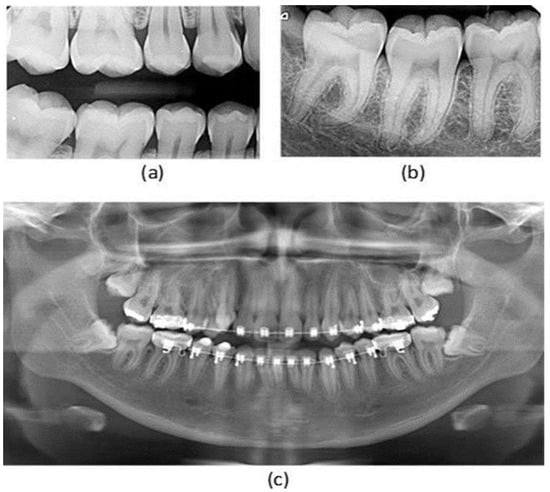

- Non-Panoramic Images: Radiographs such as periapical, bitewing, or CBCT scans that do not meet the panoramic format requirement.